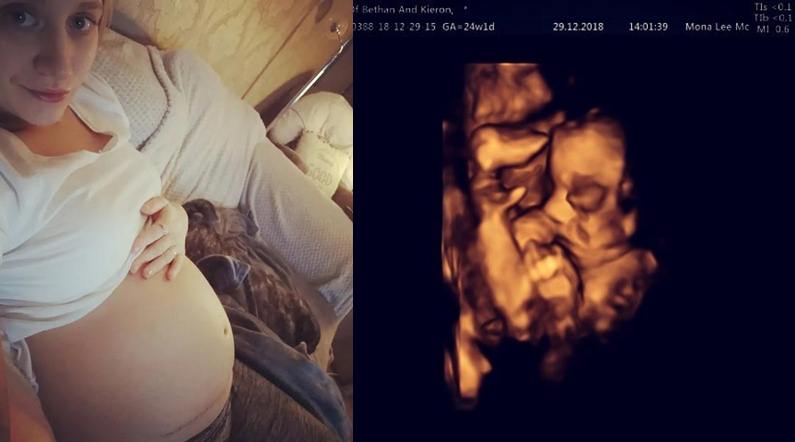

Britanka Betan Simpson (26) bila je dvadeset nedelja trudna kada je na kontrolnom pregledu na skeneru je otkriveno da bebina glava nije bila u pravilnom položaju… i da se zbog toga kičmena moždina nije razvila kako treba.

Doktori su tada dijagnostifikovali „spinu bifidu“. Tako da su Betan i njen muž su mogli da biraju između tri mogućnosti: nastavak trudnoće, prekid ili operaciju fetusa. Betani se odlučila operaciju fetusa!

Betan, koja treba da se porodi u aprilu ove godine, operisana je na Univerzitetskoj klinici u Londonu, gde su doktori pokušavali da spasu detetovu kičmenu moždinu.

Tokom operacije je beba izvučena iz utrobe, kako bi se ispravila kičmena moždina. Nakon završetka je beba vraćena i trudnoća se nastavila.

Betan je tek četvrta majka koja je prošla kroz ovu proceduru u Velikoj Britaniji. Ovu komplikovanu operaciju doktora pratili su studenti iz Londona i Belgije